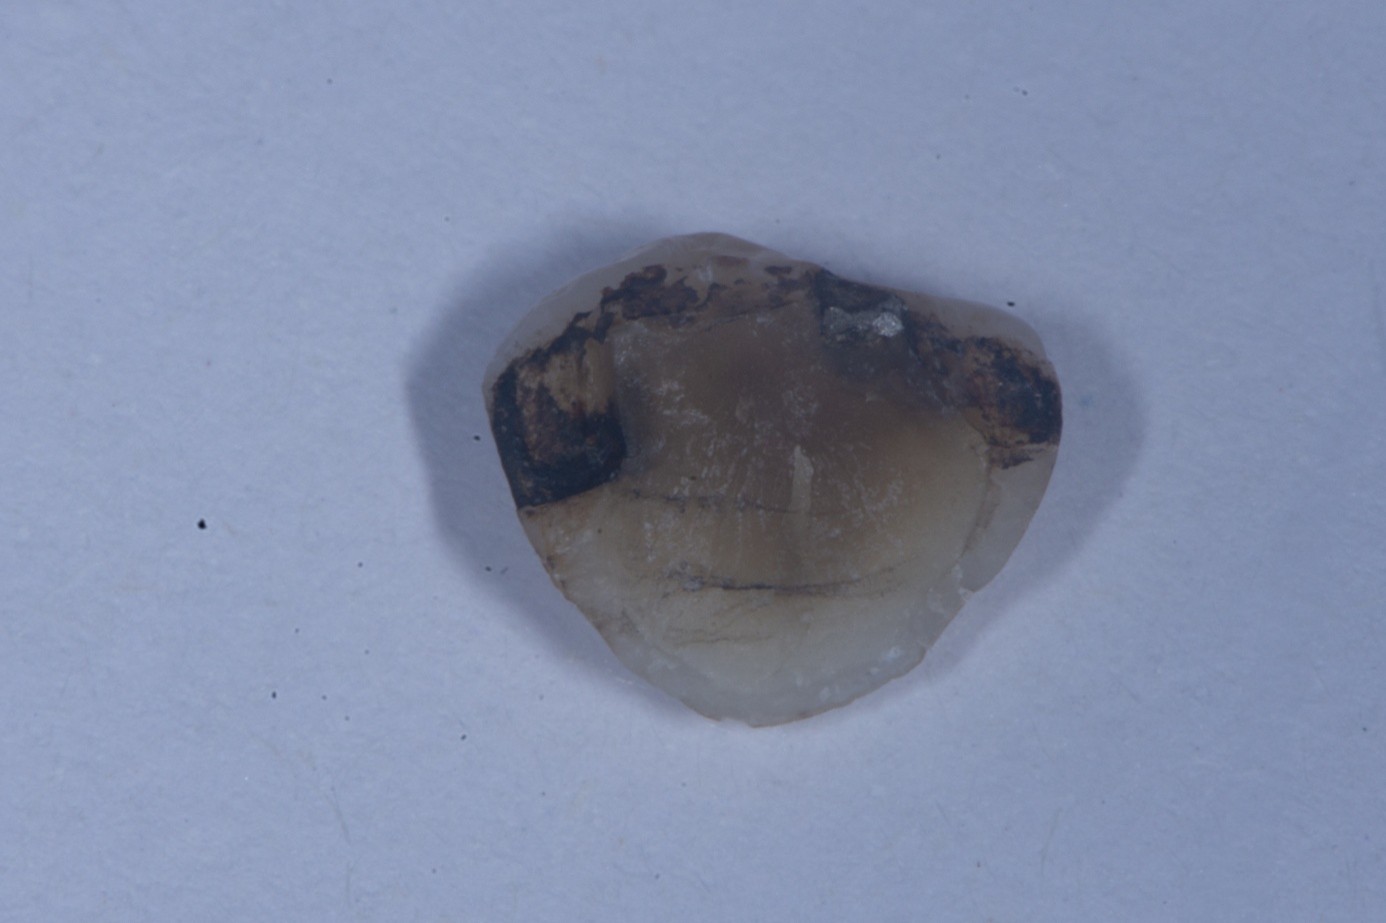

(3.) Fractured ceramic piece of the upper lateral incisor showing adhesive and cement remnants on the inner surface. (4. and 5.) At 100X magnification, the glass beads

Figure 3

(4.) appear perfectly round and smooth, lacking any sharp edges, making them ideal for cleaning glass-ceramic surfaces without causing microcracks. In contrast, aluminum oxide

Figure 4

(5.) particles show sharp, angular edges that can induce microcracks or surface damage during cleaning.

Figure 5